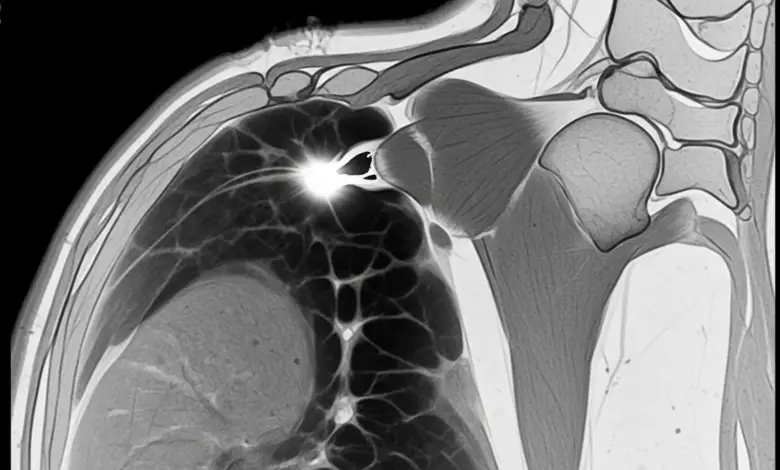

- A ressonância magnética detalha a localização e profundidade da ruptura parcial do manguito rotador e identifica edema, bursite e qualidade muscular.

A ressonância magnética detalha a localização e a profundidade da ruptura parcial do manguito rotador. O ultrassom também ajuda no seguimento quando realizado por profissional experiente.